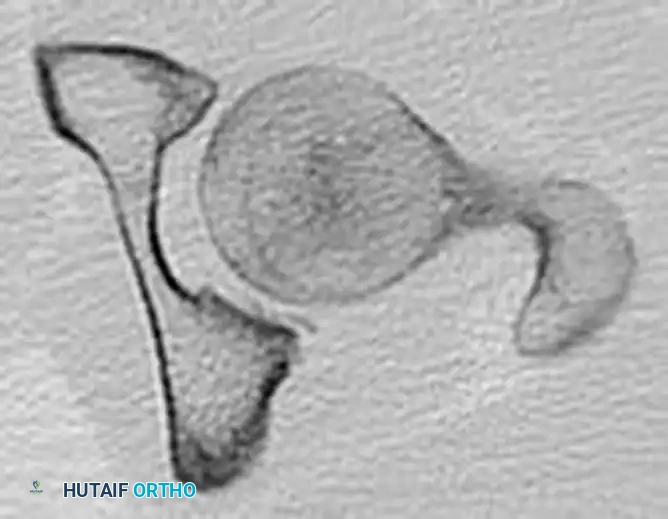

If the patient is hemodynamically stable and already in the CT scanner for a trauma pan-scan, pre-reduction axial and coronal CT images can provide invaluable information regarding intra-articular fragments and acetabular wall integrity.

FIGURE 55-52 D: Preoperative axial CT scan detailing the posterior displacement.

FIGURE 55-52 E: Additional preoperative axial CT scan highlighting the femoral head fracture.

FIGURE 55-52 F: Preoperative coronal CT scan showing the superior migration of the femoral head.